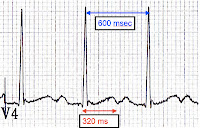

In fact, it shows an interesting similarity that all 3 groups have: the average RR was above 12/minute. In many patients, it appears to have been significantly higher- the "No Response" group had an average initial RR of 18.